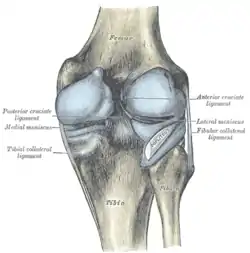

Left knee joint from behind, showing interior ligaments.

Left knee joint from behind, showing interior ligaments. Right knee-joint, from the front, showing interior ligaments.

Its anterior end is attached in front of the intercondyloid eminence of the tibia, lateral to, and behind, the anterior cruciate ligament, with which it blends; the posterior end is attached behind the intercondyloid eminence of the tibia and in front of the posterior end of the medial meniscus.

Close to its posterior attachment it sends off a strong fasciculus, the ligament of Wrisberg, which passes upward and medialward, to be inserted into the medial condyle of the femur, immediately behind the attachment of the posterior cruciate ligament.

The lateral meniscus gives off from its anterior convex margin a fasciculus which forms the transverse ligament.